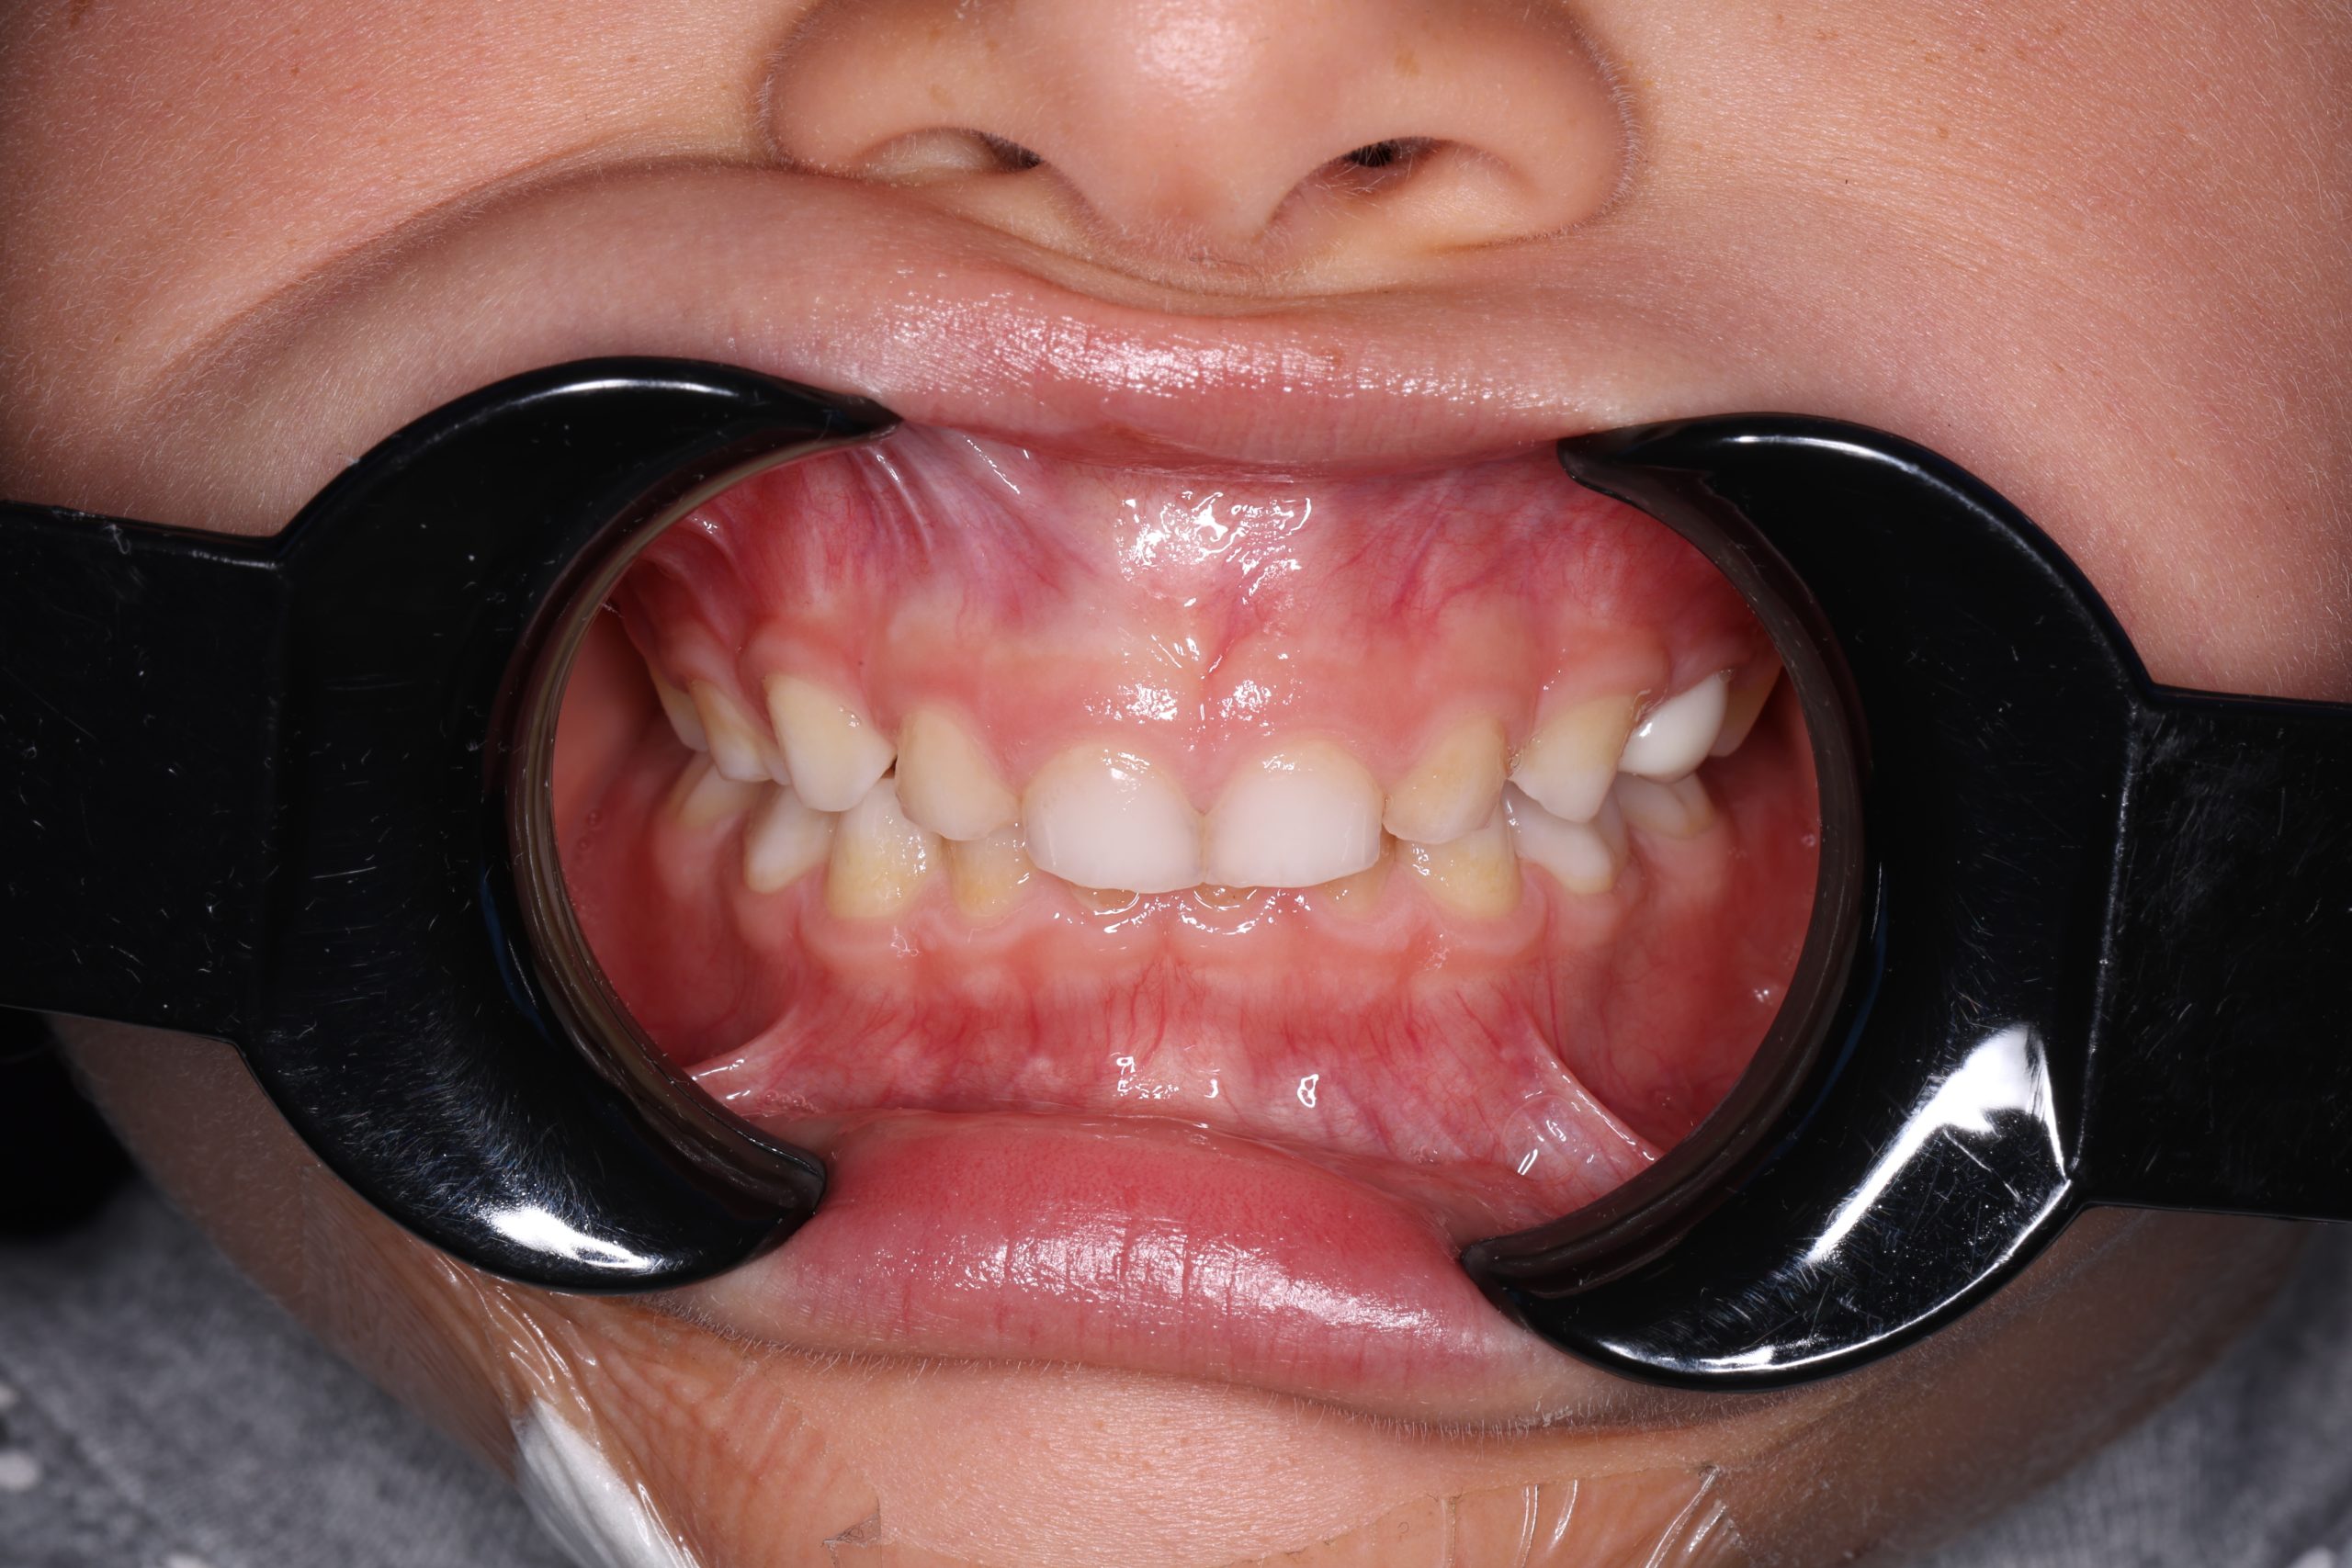

Our dentists perform root canal therapy every day. Complex anatomy and retreatments are routine. Each difficult case is planned by our senior clinician to ensure the right strategy from the start. - Microscope precision and isolation

Once numb, most patients feel only light vibration and pressure. Even severe toothache typically eases immediately after anaesthesia takes effect. - Microscope-guided access